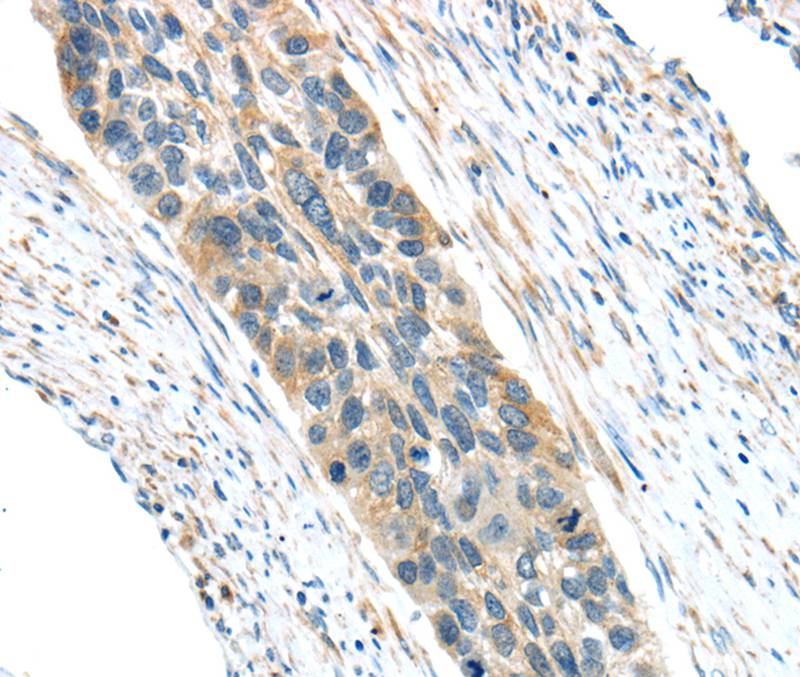

Immunohistochemical analysis of paraffin-embedded Human esophagus cancer tissue using #40403 at dilution 1/30.